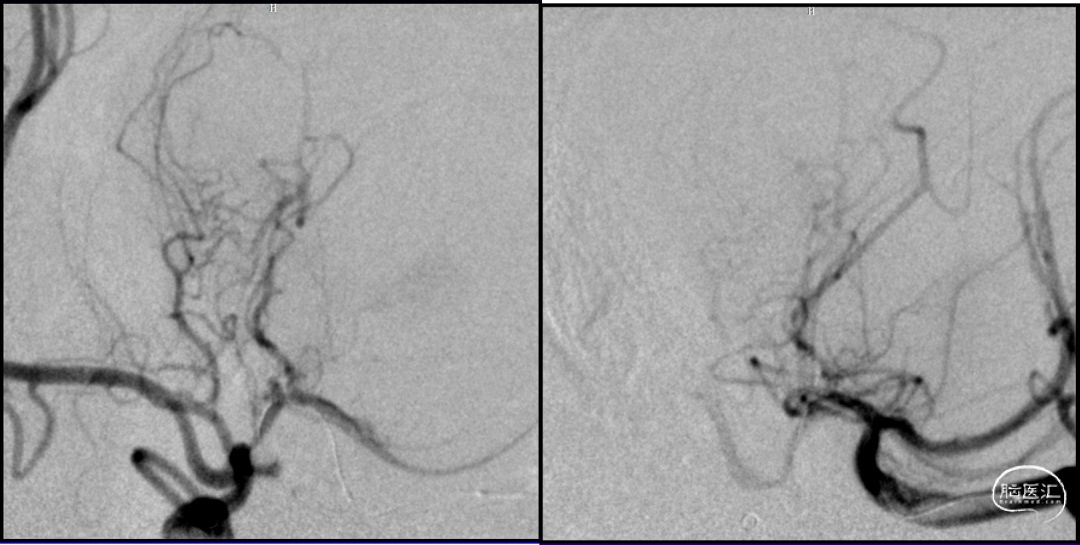

DSA

2023-08-30

前后循环3d融合寻找假性动脉瘤供血,

考虑为后交通动脉